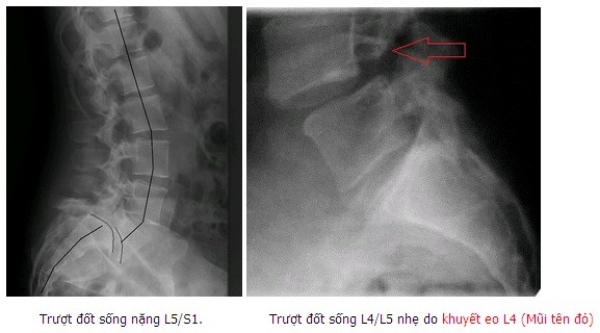

Trượt đốt sống là hiện tượng dịch chuyển của đốt sống trên so với phía dưới. Trượt đốt sống vùng thắt lưng cùng do nhiều nguyên nhân nhưng hay gặp nhất là thoái hóa và khuyết hở eo đốt sống, do chấn thương hoặc do thầy thuốc gây ra … Hầu hết các bệnh nhân trượt đốt sống vùng thắt lưng cùng có diễn biến âm thầm, không có triệu chứng. Khi đến viện khám thường đã có triệu chứng chèn ép thần kinh, đau cột sống thắt lưng do mất vũng, thậm chí có thể liệt, biến đổi tư thế vùng cột sống thắt lưng cùng ảnh hưởng đến dáng đi [1]. Phẫu thuật điều trị trượt đốt sống thắt lưng được chỉ định khi điều trị nội khoa và phục hồi chức năng không đáp ứng nhằm mục đích giải ép thần kinh và cố định làm vững chắc cột sống.

Trượt ở L45 chiếm tỷ lệ cao nhất với 50% (17 BN), có 11 BN (32,3%) trượt ở 2 tầng đốt sống. Phần lớn bệnh nhân trợt độ 1 theo phân loại của Meyerding (31 BN chiếm 91,2%). Nguyên nhân trượt chủ yếu là do thoái hóa 28 BN (82,3%), có 4 BN trượt sau mổ cột sống trong đấy có 2 bệnh nhân sau mổ thoát vị đĩa đệm và 2 bệnh nhân sau mổ cố định cột sống. Có 29 BN (86,3%) có dấu hiệu mất vững cột sống biểu hiện bằng tăng độ động trên xquang vùng cột sống thắt lưng cúi ưỡn.

Trên xquang: Trượt ở L45 chiếm tỷ lệ cao nhất với 50% (17bn), có 11bn (32,3%) trượt ở 2 tầng đốt sống tương tự với các nghiên cứu khác trượt ở vị trí L45 gặp nhiều nhất, tuy nhiên tỷ lệ trượt 2 tầng trong nghiên cứu của chúng tôi gặp nhiều hơn như Nguyên Vũ chỉ có 7,8% bệnh nhân trượt 2 tầng [4]. Nguyên nhân trượt chủ yếu là do thoái hóa 28 BN (82,3%), có 4 BN trượt sau mổ cột sống trong đấy có 2 BN sau mổ thoát vị đĩa đệm và 2 BN sau mổ cố định cột sống, tỷ lệ này khác so với các nghiên cứu của Nguyên Vũ và Võ Văn Thanh đều thấy tỷ lệ gặp nguyên nhân hở eo là nhiều hơn [4], [5]. Phần lớn bệnh nhân trượt độ 1 theo phân loại của Meyerding (31 BN chiếm 91,2%), tỷ lệ này cao hơn so với Nguyễn Vũ (trượt độ 1 chiếm 72,3%) [4]. Có 29 BN (86,3%) có dấu hiệu mất vững cột sống biểu hiện bằng tăng độ động trên xquang vùng cột sống thắt lưng cúi ưỡn.